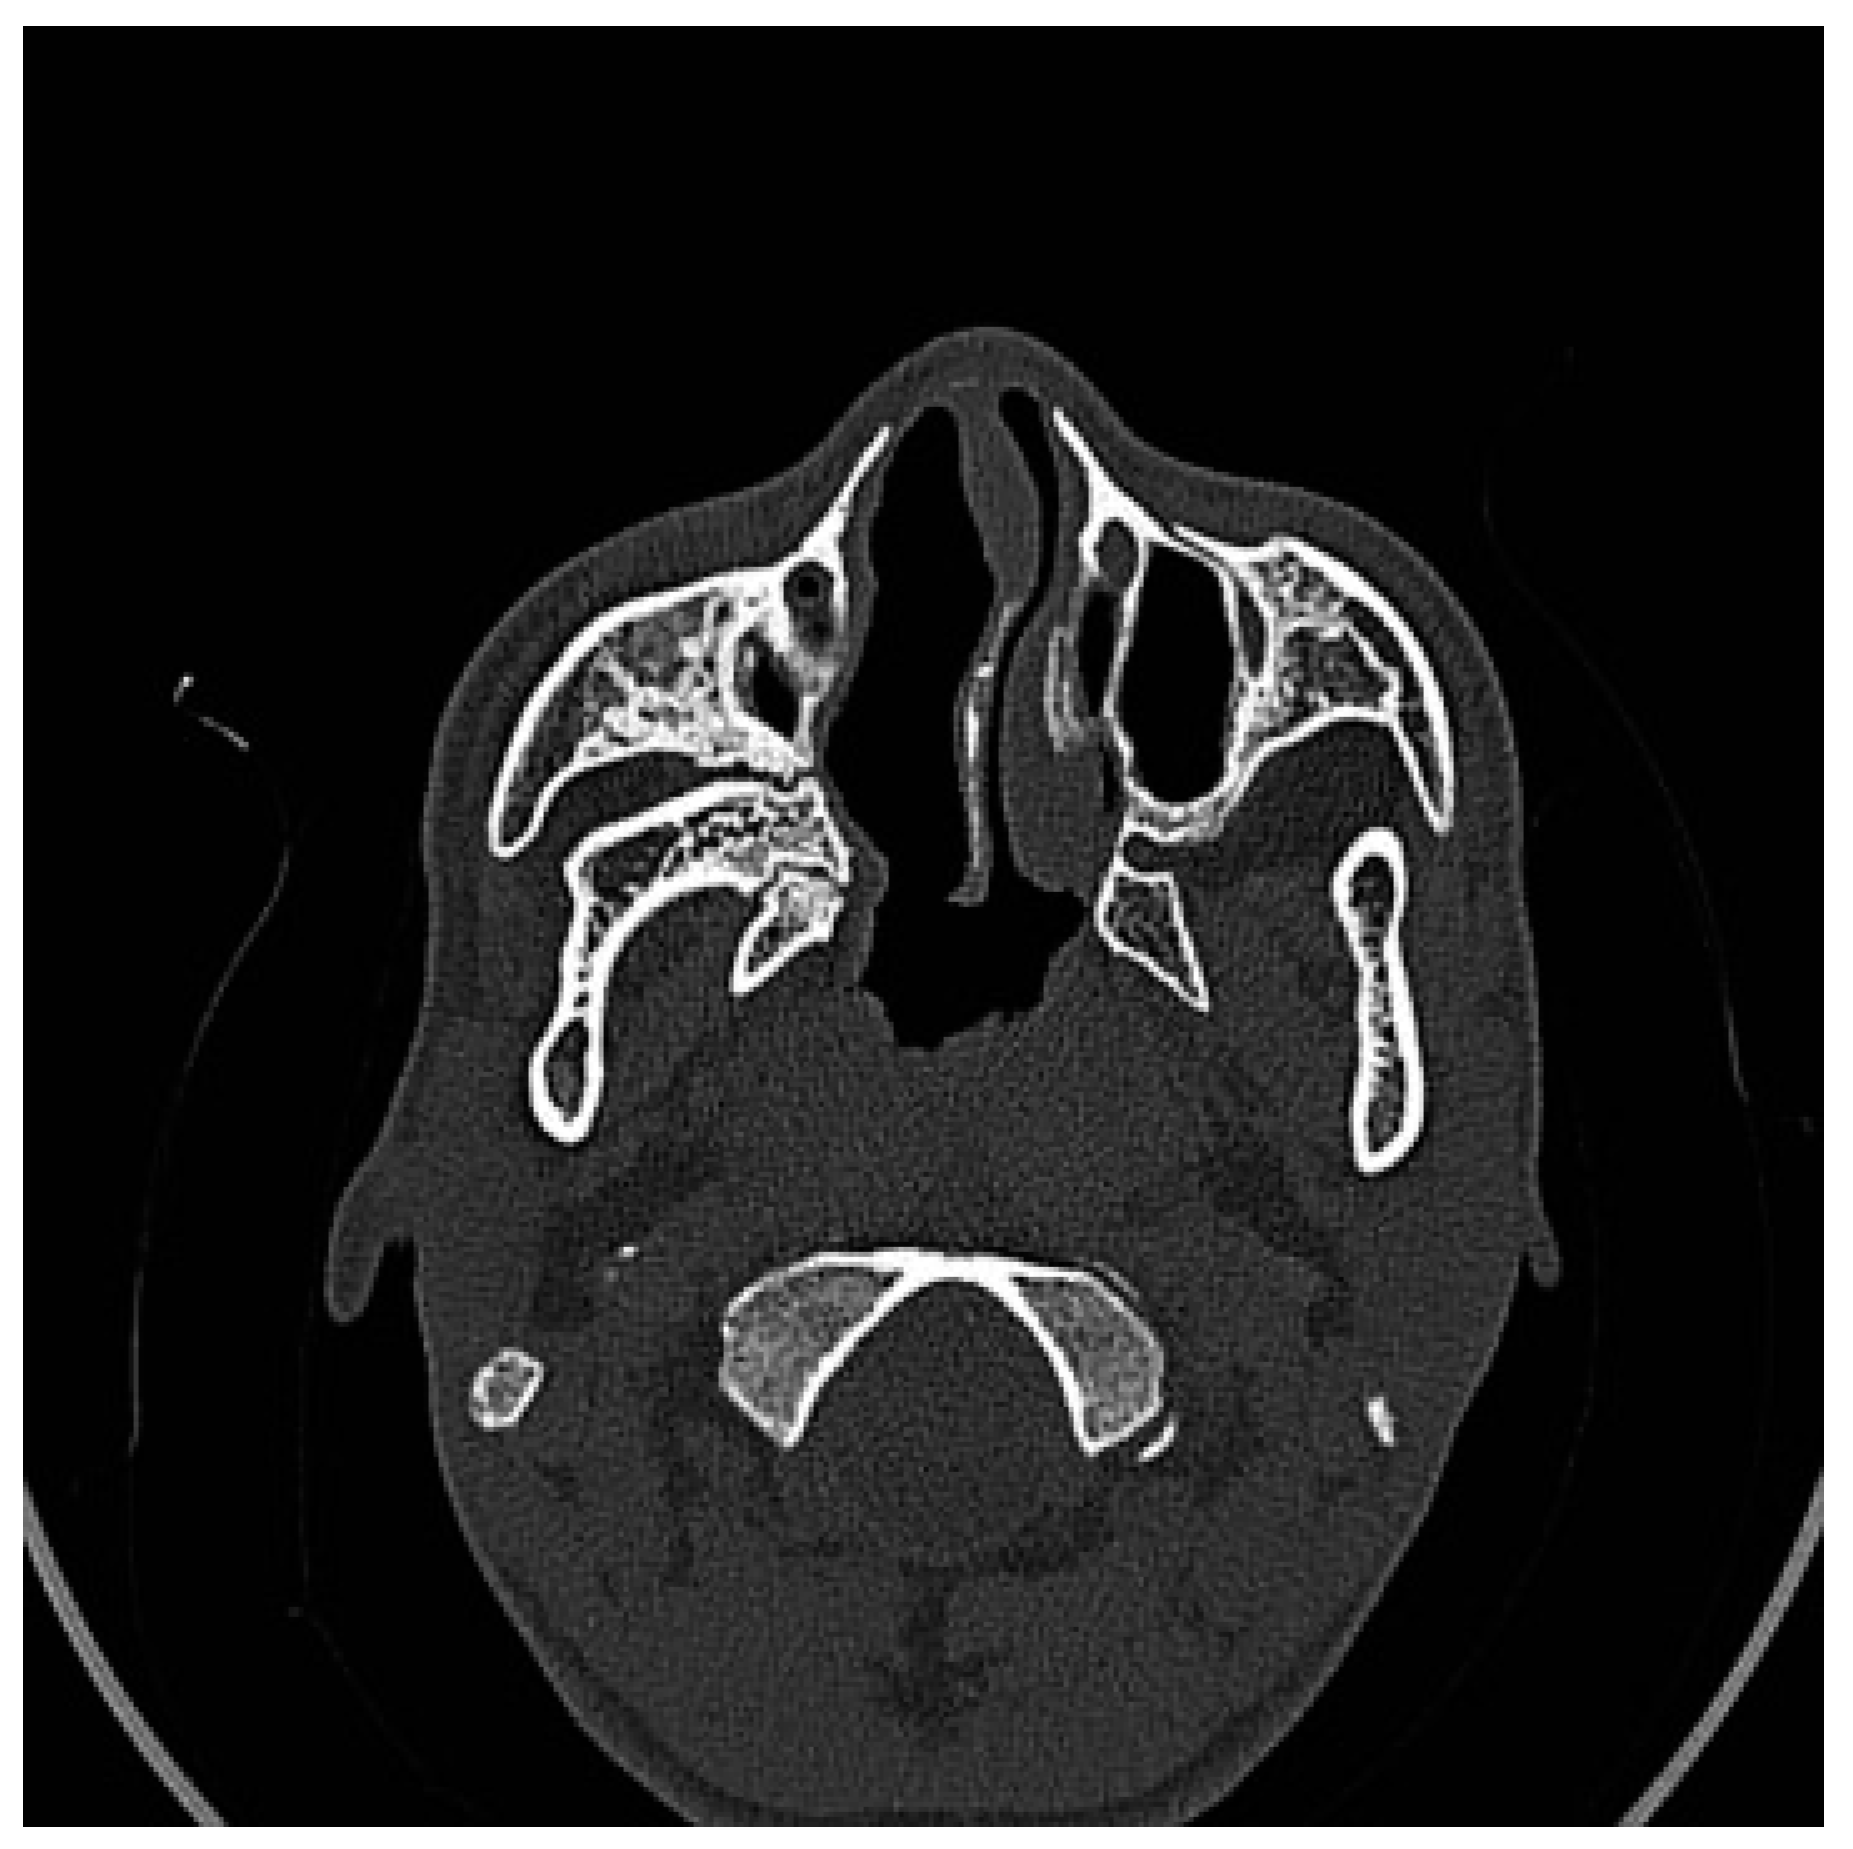

Figure 1. Preoperative CT scan. Axial view: right maxillomandibular fusion.

A CT scan of the head with 3D reconstruction (Figure 1, Figure 2, Figure 3, Figure 4 and Figure 5) confirmed a maxillomandibular fusion associated with a cleft palate, agenesis of the right turbinate, and right hemifacial microsomia (Laster type 2b syngnathia). Both temporomandibular joints (TMJs) were normal and showed no bony ankylosis (fibrous ankylosis could not be excluded with the given data).

Figure 2. Preoperative CT scan. Axial view: agenesis of the right turbinate and cleft palate.